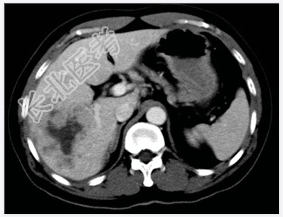

- [材料题] 患者,男性,52岁,因右上腹痛1个月、加重3天入院。体查:肝不大,肝区触痛明显,脾不大。实验室检查血AFP明显增高。行上腹部CT平扫+增强扫描。

- 简答题1、患者的诊断及依据是什么?

- 简答题2、鉴别诊断有哪些?